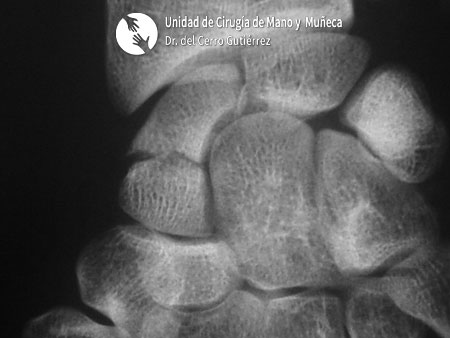

Pseudoartrosis del tercio medio

Fractura del Escafoides Pseudoartrosis del tercio medio

Fractura del escafoides. Pseudoartrosis del tercio medio

Pseudoartrosis. Inestabilidad Dorsal del Segmento Intermedio. DISI